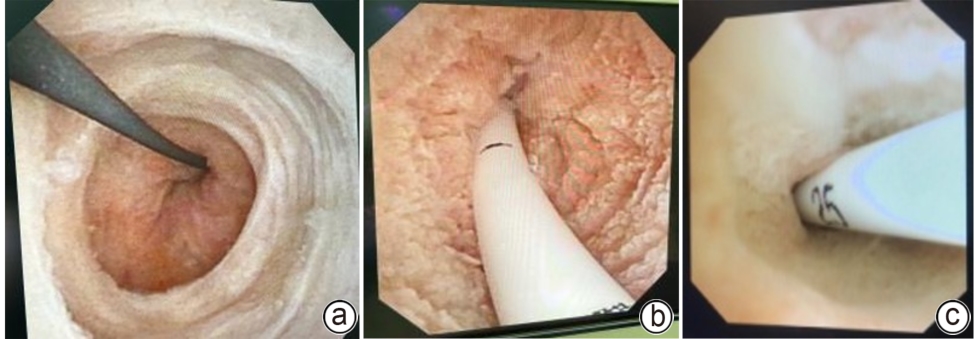

DOI: 10.12449/JCH251124

Objective To investigate the safety and feasibility of intra-biliary drainage tube placement after laparoscopic common bile duct exploration in elderly patients with choledocholithiasis, and to provide more options for surgical procedures in the clinical management of elderly patients with choledocholithiasis. Methods A retrospective analysis was performed for the clinical data of 52 elderly patients with choledocholithiasis who were admitted to Department of Hepatobiliary Surgery, Affiliated Dalian Friendship Hospital of Dalian Medical University, from November 2021 to October 2024. According to the biliary drainage method after surgery, the patients were divided into internal drainage group with 24 patients and T-tube drainage group with 28 patients, and there were 19 patients in each group after propensity score matching. The two groups were compared in terms of perioperative parameters and postoperative complications. The Wilcoxon rank-sum test was used for comparison of continuous data between two groups, and the chi-square test or the Fisher’s exact test was used for comparison of categorical data between two groups. Results Compared with the T-tube drainage group, the internal drainage group had a significantly shorter length of postoperative hospital stay and a significantly lower volume of postoperative bile loss (Z=-2.845 and -5.633, both P<0.05), while there were no significant differences between the two groups in time of operation, intraoperative blood loss, and drainage tube indwelling time (all P>0.05). There were no significant differences between the two groups in postoperative bile leak, stone recurrence, biliary stricture, and drainage tube-related complications, and the internal drainage group had a significantly lower total complication rate than the T-tube drainage group [1 (5.3%) vs 7 (36.8%), P<0.05]. Conclusion For elderly patients with choledocholithiasis, intra-biliary drainage tube placement after laparoscopic common bile duct exploration can shorten the length of postoperative hospital stay, reduce bile loss, and lower the incidence rate of postoperative complications, thereby helping to accelerate postoperative recovery.